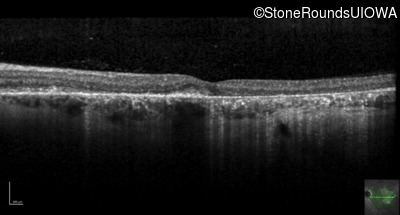

Optical Coherence Tomography - Left - 20/20 -2

Exemplar / OCT Stack

OCT Stack